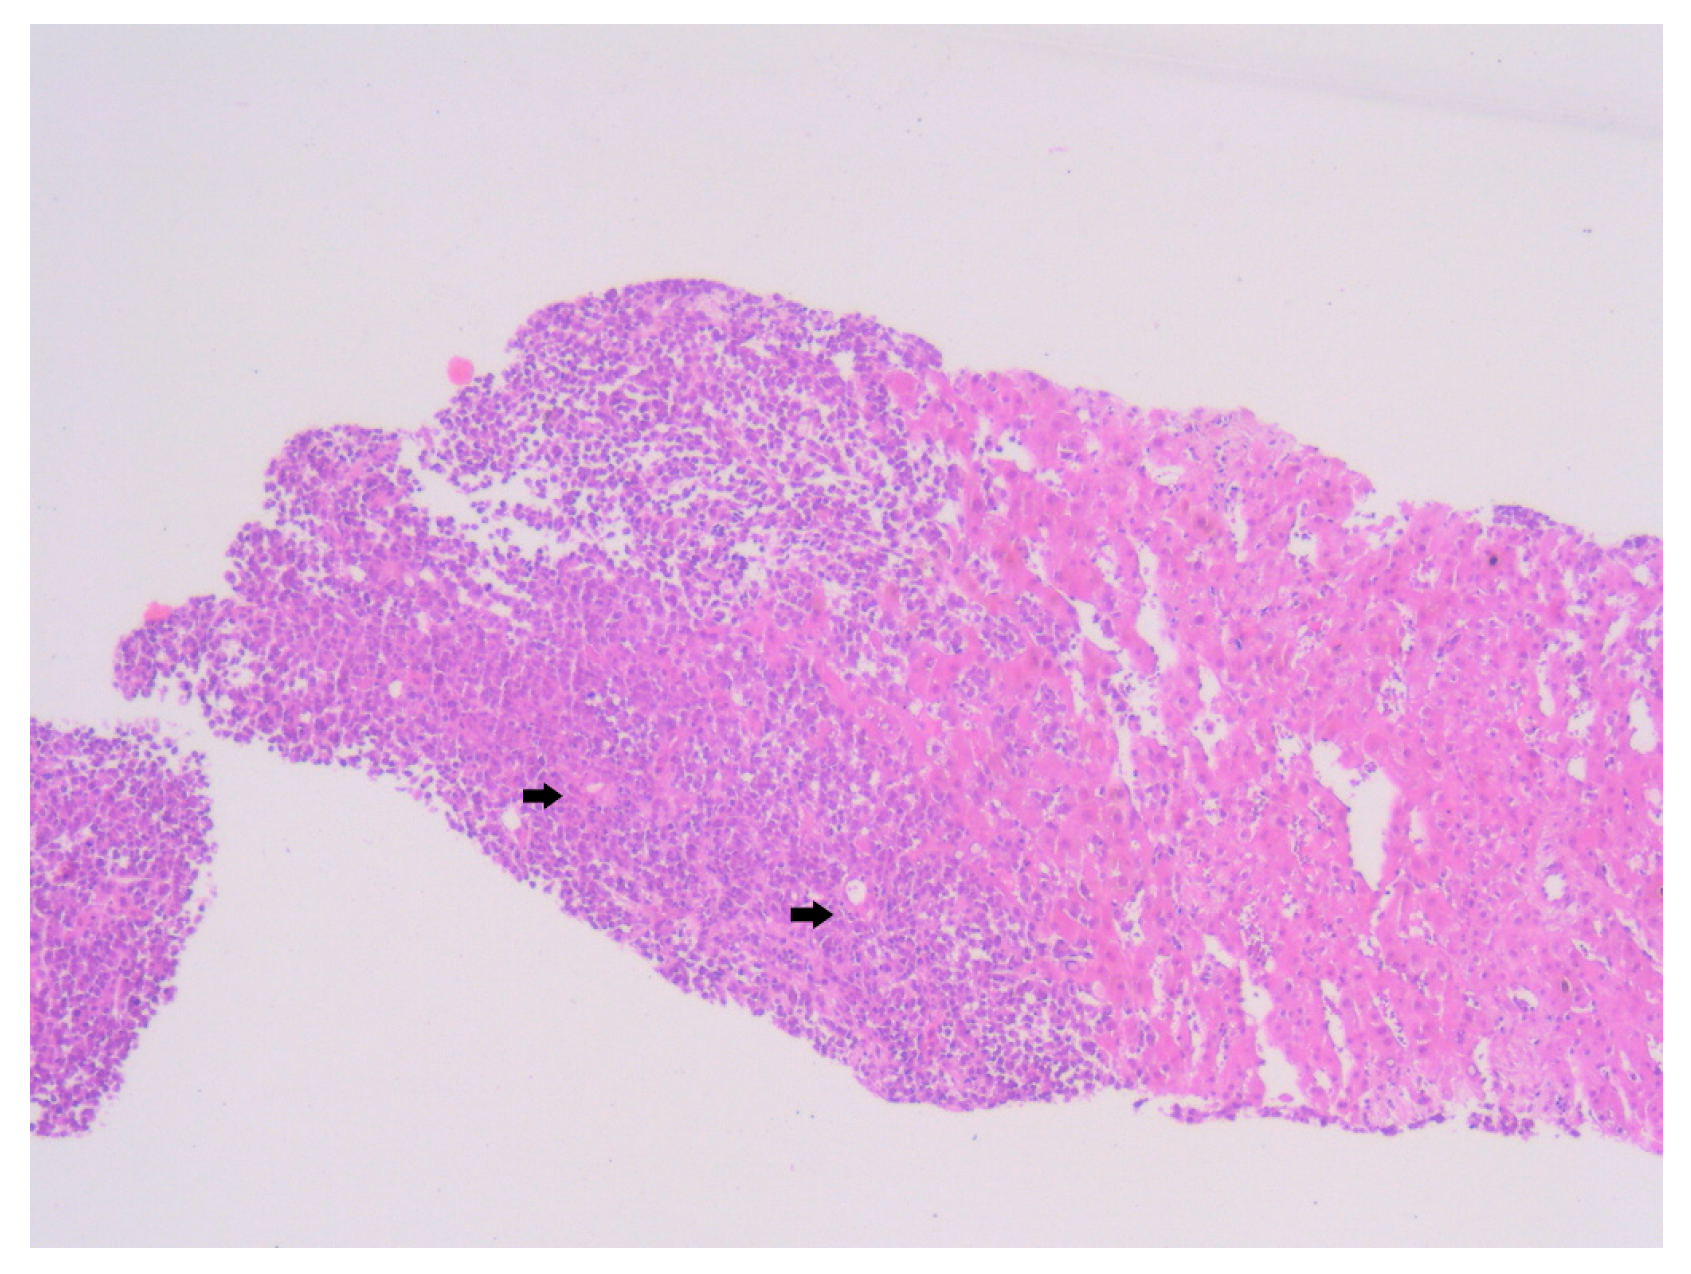

Histopathological examination of the liver biopsy revealed fragments of hepatic parenchyma measuring 10 × 1 mm, with tumoral infiltration by small, round blue cells exhibiting indistinct cytoplasmic borders, scant eosinophilic cytoplasm and round to oval nuclei that were either hyperchromatic or euchromatic, with finely granular chromatin and absent nucleoli. Occasional mitotic figures (4 per 3 HPFs) were identified. The morphology was consistent with a small round blue cell tumor, raising differential diagnostic considerations (Figure 4, Figure 5 and Figure 6). Small round blue cell tumors involving the liver include lymphoma, plasmacytoma, metastatic small-cell lung carcinoma, high-grade neuroendocrine carcinoma, metastatic melanoma, metastatic neuroblastoma and Ewing sarcoma. In contrast to these entities, MCC usually presents with a rapidly growing cutaneous primary tumor, satellite or in-transit metastases and early involvement of regional lymph nodes, as seen in our patient. The combination of morphology (small round blue cells with scant cytoplasm and neuroendocrine features), the presence of a violaceous primary lesion on a sun-exposed site, satellite nodules, marked axillary lymphadenopathy and rapid multiorgan dissemination made MCC the most consistent diagnosis, despite the absence of immunohistochemistry. To clarify the cellular origin and reach a definitive diagnosis, correlation with clinical and paraclinical data, along with immunohistochemical testing (e.g., CK AE1/AE3, CK20, CD56, Chromogranin A, SOX10, CD20, CD3, CD138), would have been essential. The liver biopsy was obtained while the patient was hemodynamically unstable, and within hours he developed biopsy-related hemoperitoneum, shock and multiorgan failure, requiring transfer to the ICU. Due to the rapid clinical deterioration and death shortly afterward, the sample could not be processed for IHC in time, and further invasive tissue sampling was no longer ethically indicated. Nevertheless, the combination of clinical presentation (violaceous cutaneous tumor with satellite nodules), imaging (multiorgan metastases) and morphology of the liver sample (small round blue cells with neuroendocrine features) supported the presumptive diagnosis of metastatic MCC. According to the 8th edition of the American Joint Committee on Cancer (AJCC) staging system for MCC, this case corresponds to Stage IV—cT2N3M1c disease. The T2 classification applies because the primary cutaneous tumor was >2 cm. N3 reflects the presence of clinically evident, macroscopic lymph node involvement together with in-transit metastases (satellite cutaneous nodules). The M1c designation is supported by multiple visceral metastases involving the liver, spleen and suspected bone lesions on CT imaging.

Figure 5. Hematoxylin–Eosin staining, 10× magnification (HE 10×): Tumoral proliferation composed of diffusely arranged cells forming sheets of variable sizes, separated by minimal stroma. Arrows highlight clusters of small round blue cells arranged in diffuse sheets.